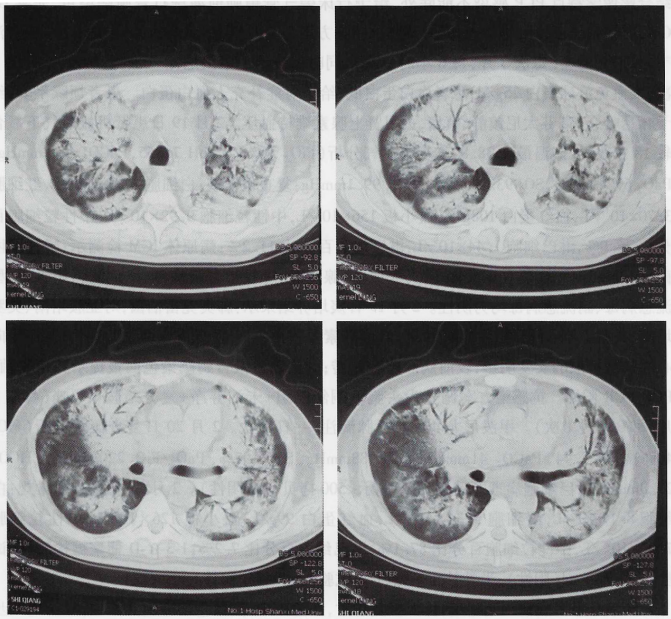

胸部CT(2016年2月6日)示双肺多发斑片状阴影(图1)。血常规(2016年2月9日,外院):WBC 21×109/L,PLT 423×109/L,NEU% 81%。血气分析(2016年2月10日,吸氧3 L/min):pH 7.43,PaO2 68 mmHg,PaCO2 37 mmHg,SaO98%,PaO2/FiO297 mmHg。

图1  2016年2月6日胸部CT:双肺多发斑片状阴影